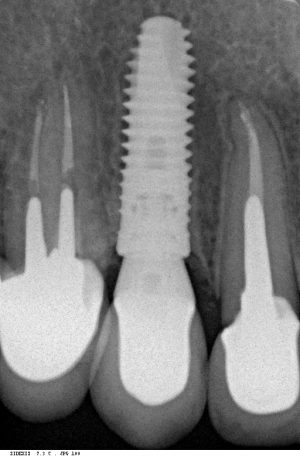

Мы сделали рентгеновские контрольные снимки —  панорамный для оценки положения имплантатов и прицельный для контроля посадки абатментов.

На последнем видно, что абатменты (особенно правого на фото зуба) не сели на свои места, между ними и платформами имплантатов есть щель — и эта ситуация наглядно демонстрирует, ПОЧЕМУ такие снимки необходимы. Мы вернули пациентку в хирургический кабинет и провели коррекцию абатмента (уменьшили ширину трансгингивальной части), После чего, проводили пациентку в кабинет стоматолога-ортопеда для временного протезирования.

После фиксации временных коронок мы делаем прицельный контрольный снимок для контроля посадки абатментов на платформу и оценки качества изготовления композитных реставраций.